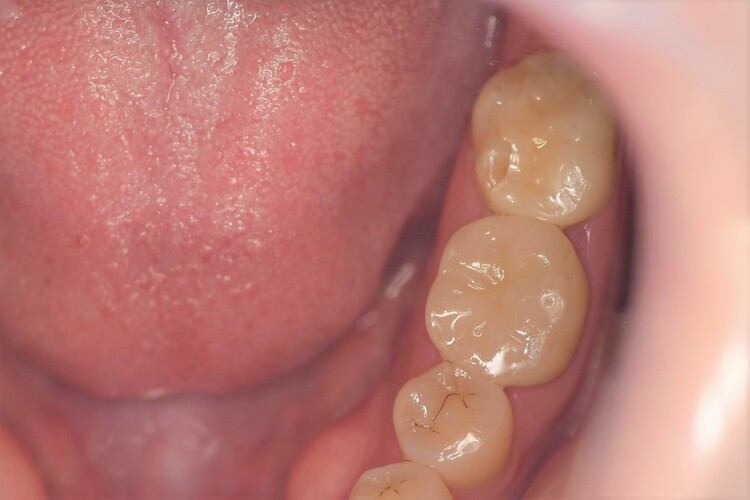

| 年齢 | 33歳 |

|---|---|

| 性別 | 女性 |

| 主訴と治療部位 | 左下7番セラミックインレーの咬合面(上下の歯の噛み合わせに接する面)に穴があいている。 |

| 治療内容 | 左下7番セラミックインレーを除去してジルコニアインレーにかえる。 |

| 治療費 | 合計44,000円 ジルコニアインレー44,000円×1本 (2023年1月現在) |

| 治療期間 | 2週間 |

| リスク・副作用 | ジルコニアは天然の歯よりも硬いため、噛み合わせで接する対合歯(歯)を傷つけることがある。噛み合わせがあまり強い場合はジルコニア自体が割れることもある。 |

| 治療方針 | 歯ぎしりなどによる噛み合わせの負担が強くセラミックインレーだと割れてしまうリスクがあるので、セラミックより硬いジルコニアインレーで進めた。 |

| 特記事項 | 対合歯が削れる可能性があるので就寝時にマウスピースを使っていただくようご提案した。 |

| 担当者所見 | 色味が綺麗に仕上がりました。 |